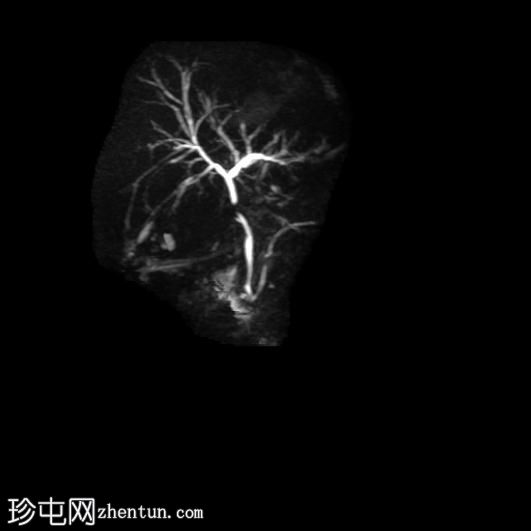

MRCP

厚层扫描

胆囊切除术后,可见肝总管局部断裂,尤其是在胆囊管开口上方。该断裂伴有胆囊切除部位形成较大的血肿或胆汁瘤。